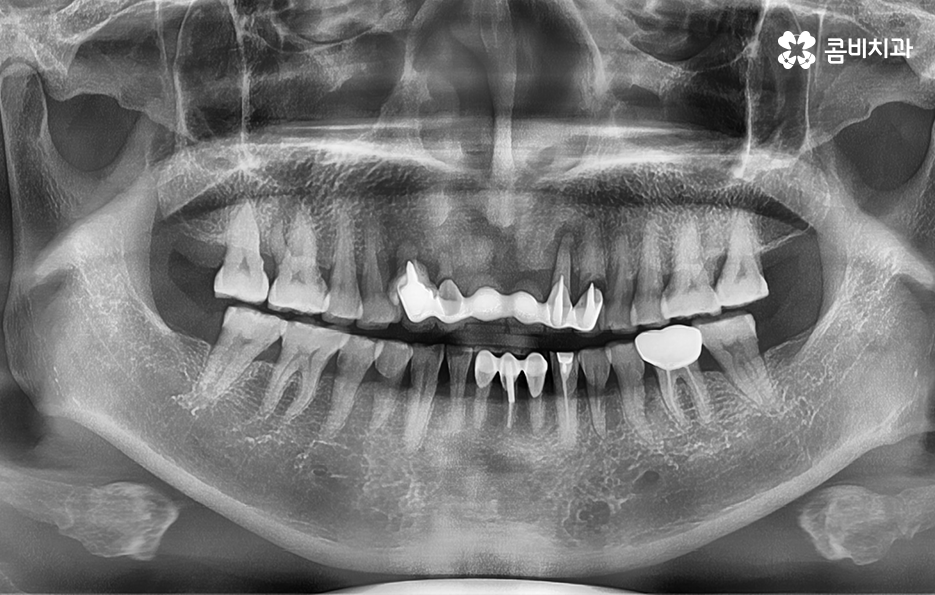

오늘 포스팅의 사례의 경우 앞니를 이미 잃은 상태였지만 주변 치아를 활용하여 브릿지로 연결해놓은 상태에서 기존의 치아가 버티지 못하여 앞니임플란트 하게 된 경우라고 볼 수 있는데요.

일반적으로 앞니의 주된 상실 요인은 젊은 분들의 경우 사고나 충치로 인한 경우가 많지만 중년 이후에는 치주질환으로 인해 잇몸이 약해져서 치아를 상실하는 풍치로 인한 경우가 많을 거예요.

잇몸 상태와 전신 건강이 양호한 경우에는 원데이임플란트를 통해 앞니임플란트 치료를 많이 진행하지만 오늘 케이스처럼 이미 치아를 발치한 후 시간이 지난 경우나 치주염으로 인해 잇몸 뼈가 녹고 염증이 심한 경우에는 빠른 치료보다는 잇몸을 충분히 회복하여 건강하고 안전한 결과에 더 초점을 두고 있는데요.